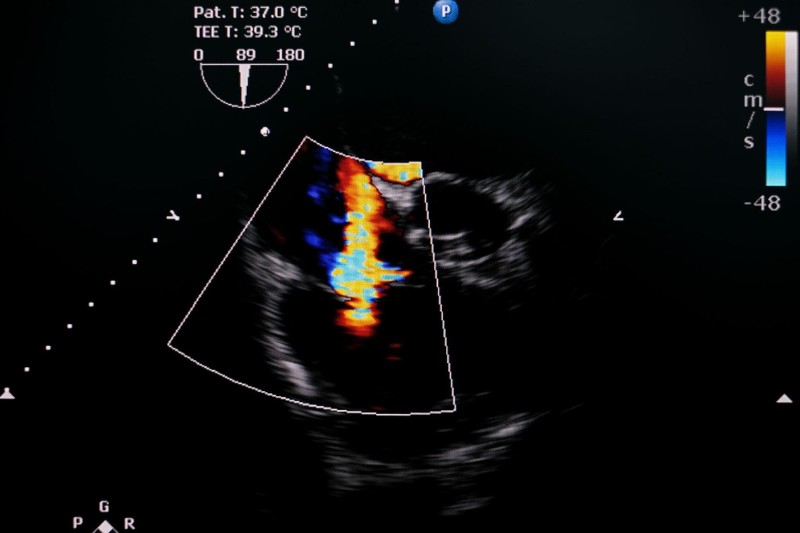

Để hiểu rõ hơn về hở van tim 3 lá là như thế nào, hãy cùng theo dõi những hình ảnh sau:

Siêu âm tim 2D, 3D là phương pháp phổ biến để chẩn đoán hở van tim 3 lá. Siêu âm tim qua thành ngực giúp phân biệt hở van nguyên phát (do tổn thương lá van) với hở van chức năng (do bệnh lý thất phải hoặc tăng áp phổi). Đồng thời, phương pháp này đánh giá:

Siêu âm tim qua thực quản cho hình ảnh chi tiết hơn trong trường hợp siêu âm thành ngực không rõ ràng. Tuy nhiên, kết quả dễ bị ảnh hưởng bởi thuốc gây mê, do đó, bác sĩ thường ưu tiên đánh giá bằng siêu âm thành ngực trước.